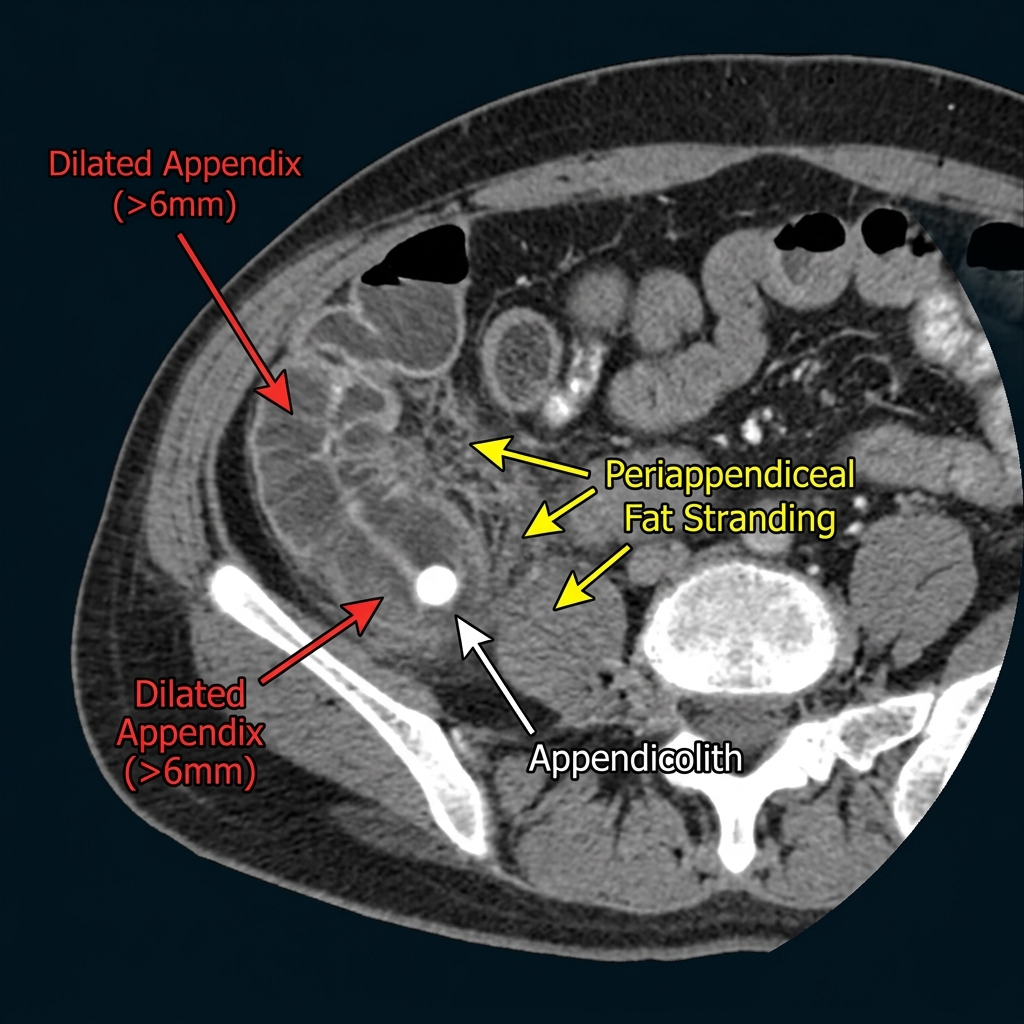

A complete guide to CT diagnosis of acute appendicitis. Learn the classic and complicated CT findings, differential diagnosis, pediatric considerations, and structured reporting for appendicitis.